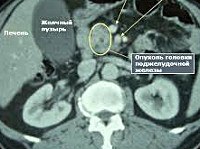

Наиболее информативными методами диагностики доброкачественных опухолей поджелудочной железы в гастроэнтерологии являются инструментальные исследования. УЗИ органов брюшной полости проводится с целью визуализации образования, определения его размеров, состояния регионарных лимфатических узлов. Однако при гормонпродуцирующих опухолях малых размерах данный метод малоэффективен. Высокоинформативны КТ и МРТ поджелудочной железы, позволяющие обнаружить опухоли небольших размеров и детально изучить их распространенность.

Для определения доброкачественных опухолей поджелудочной железы с множественными очагами (это характерно для инсулом, гастрином) проводится сцинтиграфия – в организм вводятся радиофармпрепараты, которые активно накапливаются клетками опухоли, и их излучение фиксируется на снимке. При подозрении на гемангиому поджелудочной железы проводится ангиография с целью оценки тока крови в образовании и его связи с системным кровотоком. Для изучения гистологической структуры новообразования, дифференциации его от злокачественных опухолей осуществляется пункционная биопсия поджелудочной железы с последующим морфологическим исследованием биоптатов.